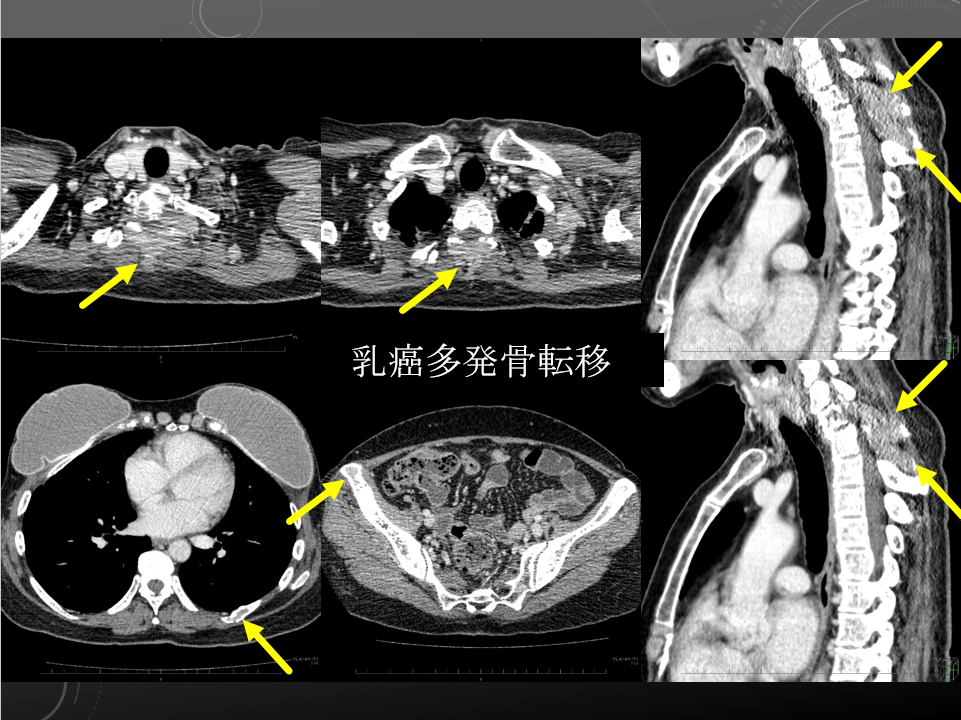

左背部の疼痛精査、転移のチェック

Th1~3の棘突起周囲を中心に軟部組織あり骨転移疑われます。

左第8肋骨の骨皮質不連続性あり、骨転移の可能性があります。

以上は左背部痛の原因と考えられます。

多発リンパ節転移もやや増大。

肝転移も図のように新たな転移も出現。

肺野では不整形高吸収域散見されます。概ね変化ありません。

activeな肺炎像や胸膜炎を示唆する所見は指摘できません。

胸腹水認めません。

その他、スキャン内で新たに出現した active lesion はありません。

左背部の疼痛精査、転移のチェック

Th1~3の棘突起周囲を中心に軟部組織あり骨転移疑われます。

左第8肋骨の骨皮質不連続性あり、骨転移の可能性があります。

以上は左背部痛の原因と考えられます。

多発リンパ節転移もやや増大。

肝転移も図のように新たな転移も出現。